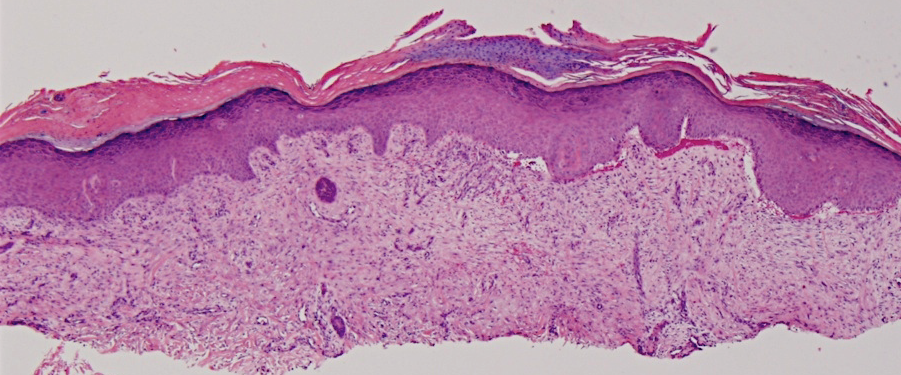

VA34: Right Temple, Actinic Keratosis, Hypotrophic, Focally reaching the base.

- White arrow denotes hair follicle